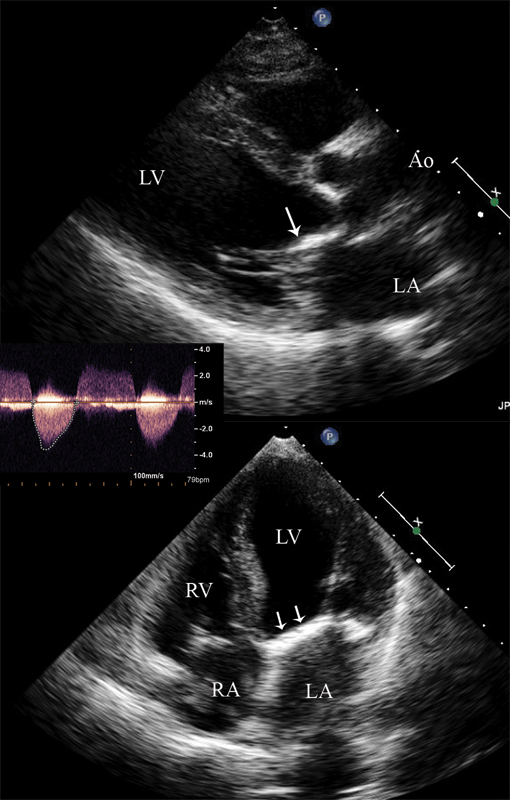

فحوصات تشخيصية لبعض امراض القلب والشرايين التاجية